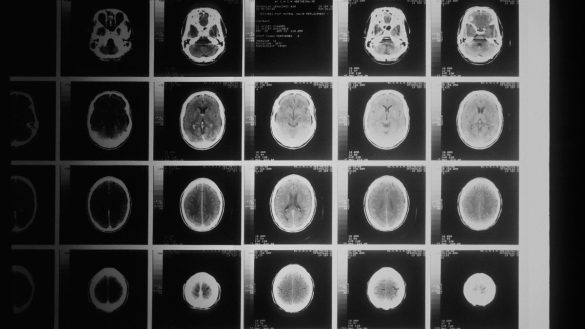

A Esclerose Múltipla é uma doença sistema nervoso central, de origem auto-imune e causa ainda desconhecida. Na Esclerose Múltipla o sistema imunitário desregulado danifica os constituintes do cérebro e da medula espinhal. Os principais alvos são as células que produzem mielina, um revestimento rico em…

A esclerose múltipla (EM) é uma doença crónica do foro neurológico que afeta o sistema nervoso central (SNC), cérebro e medula espinhal, com evolução progressiva e incapacitante. Em Portugal, estima-se que a doença alcance cerca de 60.000 a 100.000 habitantes. Atinge com maior frequência o…